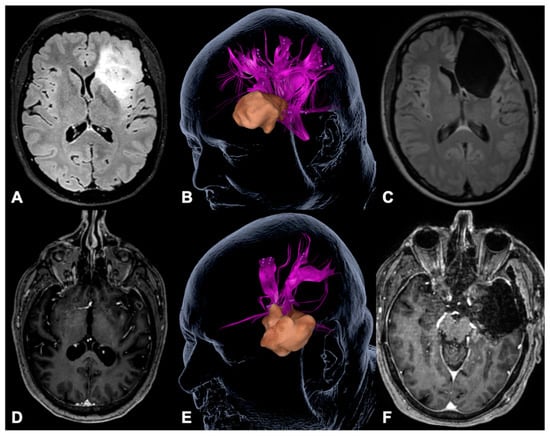

- Negwer, C.; Ille, S.; Hauck, T.; Sollmann, N.; Maurer, S.; Kirschke, J.S.; Ringel, F.; Meyer, B.; Krieg, S.M. Visualization of subcortical language pathways by diffusion tensor imaging fiber tracking based on rTMS language mapping. Brain Imaging Behav. 2016. [Google Scholar] [CrossRef]